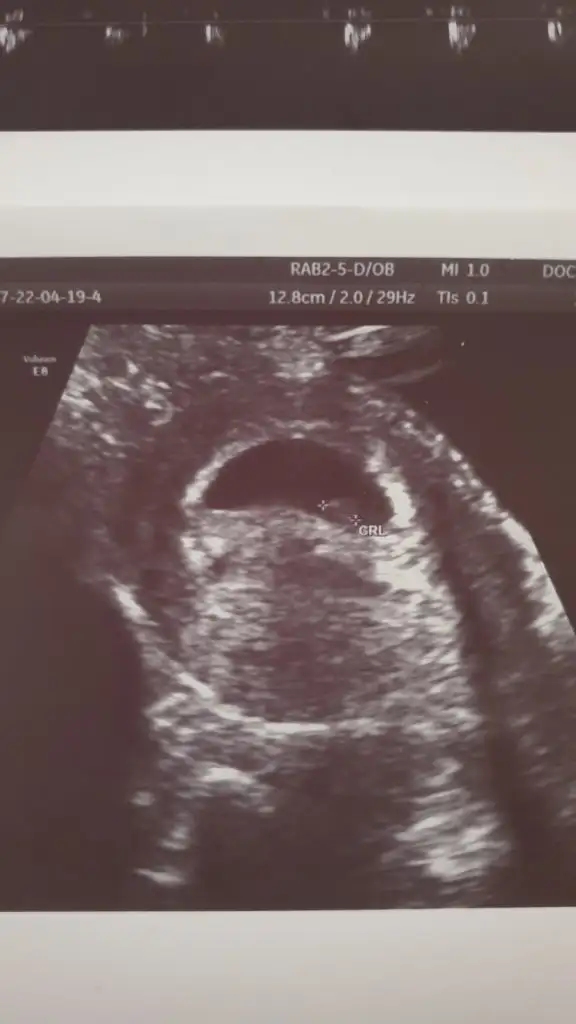

Tam tosun paşa maşallahMerhaba iyi günler bana da yorum yaparmısiniz acaba sizi gördükm sırf sizin için hesap açtım kayıt oldum ikinci gebeliğim bu cinsiyeti çok merak ediyorum 11 haftalık görüntüsü bu

İlk bebeğim kız bunun da erkek olmasını çok istiyorum gönlüm erkekten yana ama ben Instagramda cinsiyet tahmini yapan iki sayfaya tahmin yaptırmıştım onlar %70 kız dediler o günden beri bişey hissetmiyorum ama ilk hamileliğimden çok farklı geçiyorTam tosun paşa maşallahsen ne hissediyorsun canım

Bana da tahmin yapar mısınız 11 haftalık burdakarından mı canım